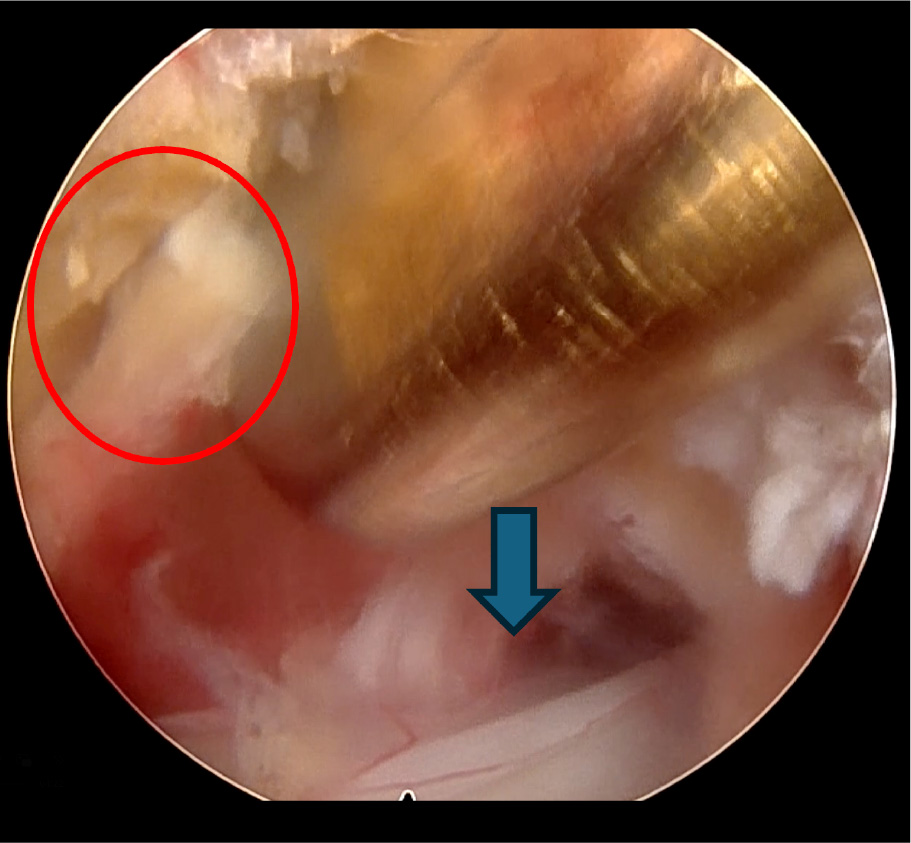

右図は背中から見た腰椎を示していますが、

少量の骨削除による開窓でヘルニアが摘出されました。